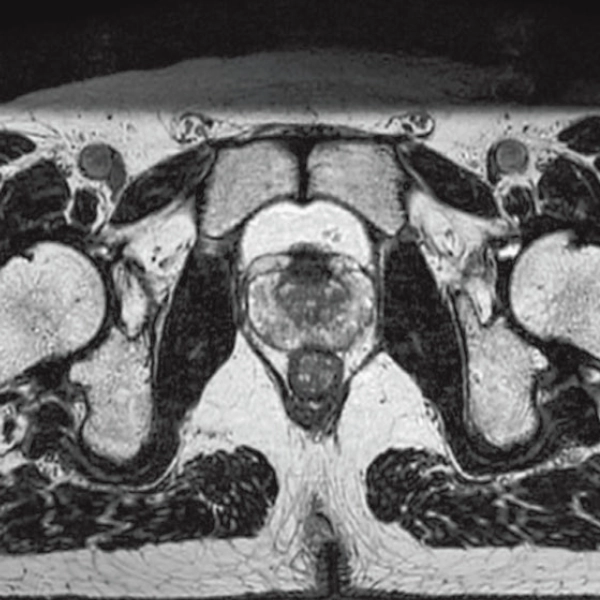

T2*WI Multi Echo,

0.38×0.38×2.0mm

0.35×0.40×3.0mm, 2:55

StillShot:The camera detects motion and suppresses the effects of body movement

FLAIR

T1WI Dual Echo (Out) Breath hold

RADAR:Body movement suppression technology for those who cannot hold still

T2*WI RADAR, 2:34

T2WI FatSat Respiratory gating RADAR, 2:16